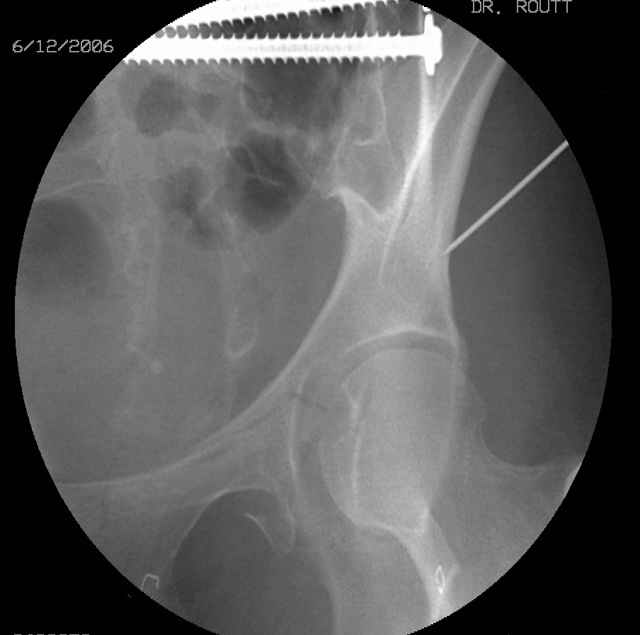

Prone

Here's a pic from the foot of the bed and you can see the clamp in the wound and the knee is extended so he must've had a tight rectus. The C-arm is rolled back to an obturator oblique image to reveal the anterior column...we put a slight outlet tilt to combine the images and give a better view of the anterior column...we can see the posterior column limb reduction in the wound, we can palpate the quadrilateral surface limb, and the image demonstrates the anterior column portion...you can adjust the tilt and rotation to image tangentially to the fracture plane if you'd like. We've inserted a 2mm K wire to site the starting point and aim/orientation for the drill and screw

Prone Imaging

same image, just another look.

Prone Inlet

OK, now we're inserting the drill percutaneosuy using a sleeve. This fluoro shot is not for this patient (notice no clamp) but I was too lazy to go searching the PACS for one with the clamp on, so pretend...I'll save the next ones and send along...the imaging is the same and the clamp doesn't obstruct imaging other than very rarely...you can always tilt the C-arm a bit to clear it if the clamp obstructs the exact spot that you'd like to see. We'll assume that everyone knows the safe zone for a medullary ramus screw. Use a calibrated drill and sleeve of known length to simplify your life...or use Alex's fancy cannulated screws...I like 3.5mm screws because the oscillating 2.5mm drill bounces and remains intraosseus when it oscillates and contacts endosteal cortical ramus... so will the screw, and like a long bent screw IF the fracture is clamped... if unclamped, when the screw contacts the endosteum, it pushes the reduction apart instead of bouncing. The big 7mm cannulated screws fit few patients and extrude...we very rarely use them any more...you'll see an old one later.